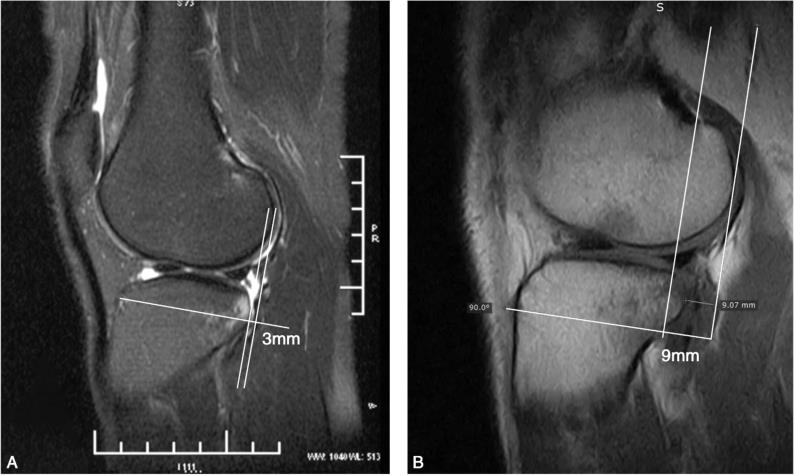

可以分别测量内侧或外侧胫骨平台前移的数值,本章节介绍外侧胫骨平台前移的测量方法。测量可以通过常规的MRI进行(图5-8),如有条件,可以进行负重位MRI测量(图5-9)。

图5-8 外侧胫骨平台前移的MRI测量

选择腓骨头显影的第一个层面,或股骨外侧髁后方正圆(红色)的层面;测量股骨后髁(蓝线)与胫骨平台后缘(绿线)软骨下骨之间的距离。

图5-9 常规MRI与站立位MRI测量胫骨前移数值的比较

A.常规平卧位MRI测量胫骨前移数值为3mm;B.同一患者站立位MRI测量胫骨前移数值为9mm。